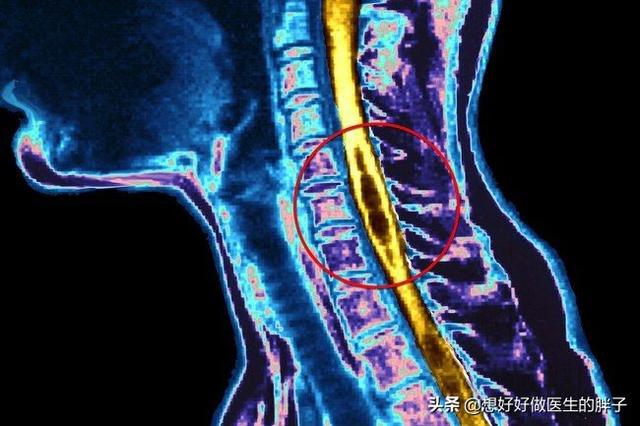

比如手麻常见的有腕管综合征、佛罗氏弓综合症等等,因为神经的挤压,所以你会出现手麻

这种也是容易误诊的,因为很多人一直认定手麻就是颈椎压迫神经,所以治疗就容易进入误区